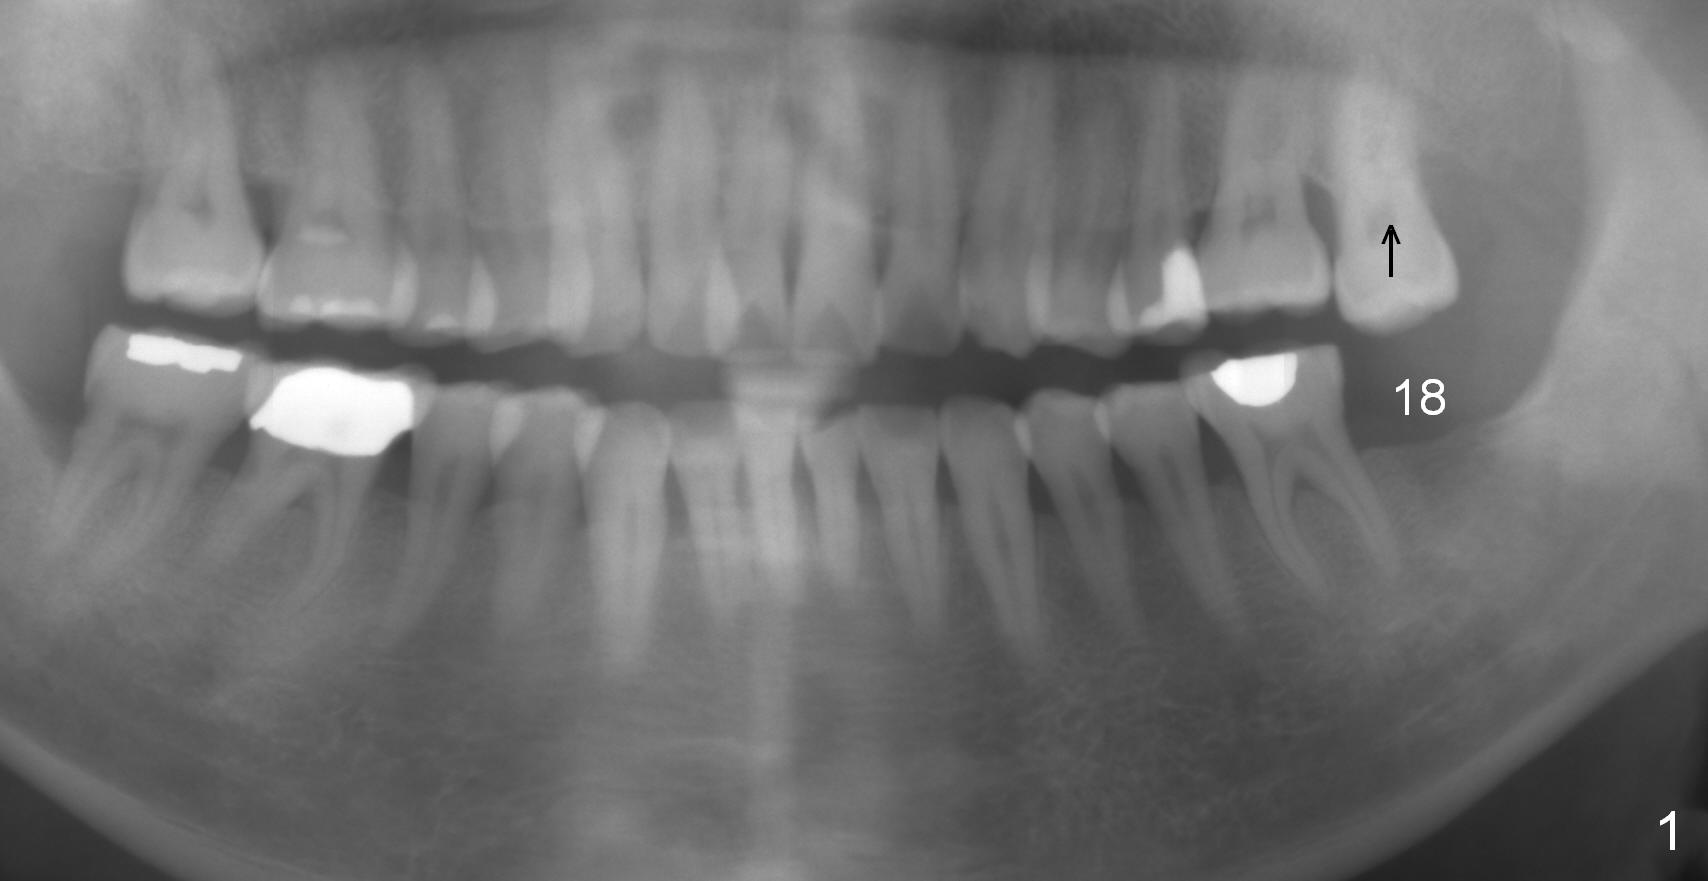

A 51-year-old man has lost #18 for more than 10 years (Fig.1,6). There appears to be sufficient bone height for implant (15 mm (Fig.7 (red dashed line: the superior border of the Inferior Alveolar Canal))). Prepare 4 mm implant spacer and SM starter drill and 2 mm pilot drill at 12 mm. Take PA. Palpation reveals that the edentulous ridge is wide. Place an implant in the middle of the ridge (buccolingually).

Next appointment, place 2 of mini-implants for #15 intrusion (Fig.1 arrow): one in MB (latch driver) and the other in DL (hand instrument).

In fact, the tooth 15 had basically no extrusion 6 years earlier (Fig.2) with even occlusal plane. When the tooth is intruded orthodontically, the occlusal plane may be not even (Fig.3). When the implant at #18 osteointegrates (Fig.4 green), fabricate a provisional (grey rectangle) with higher mesial occlusal surface. For certain period of time, the tooth #15 may change its axis so that the mesial portion of the tooth may be intruded more (Fig.5 arrow).